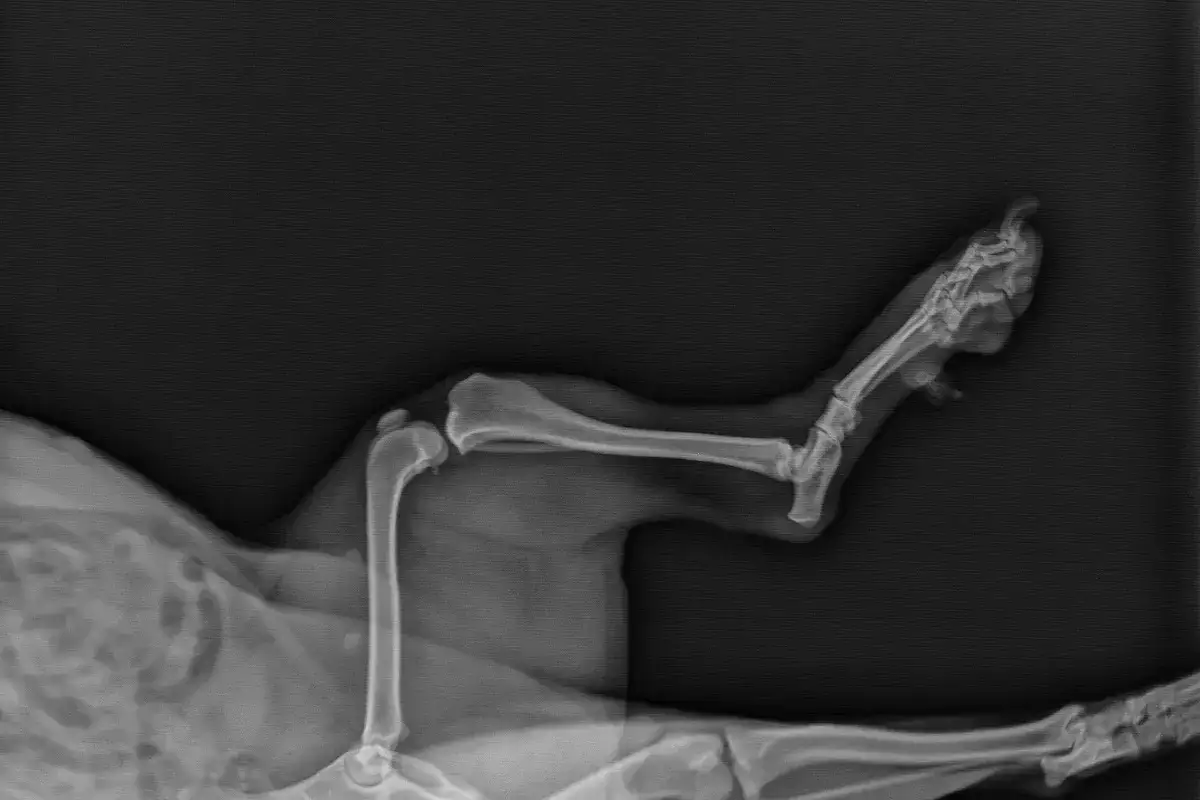

Zdjęcia rentgenowskie pomagają ocenić ustawienie kości, obecność zmian zwyrodnieniowych i ewentualne inne urazy. Przy planowaniu operacji czasem potrzebna jest dokładniejsza diagnostyka obrazowa, zwłaszcza gdy podejrzewa się deformacje osi kończyny.